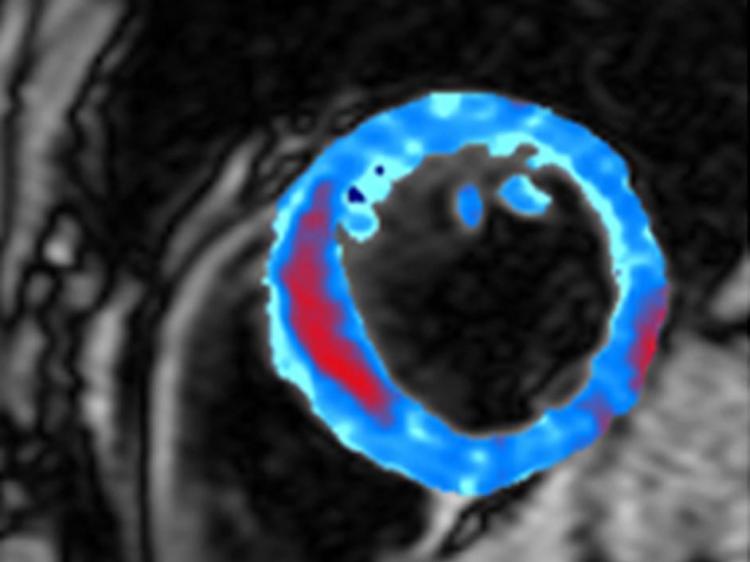

Bleeding inside the heart after a heart attack has been discovered through unprecedented images published this week.

Scientists captured Magnetic Resonance Imaging (MRI) scans of such bleeding from 15 recent heart attack sufferers from Imperial College Healthcare NHS Trust.

Dr Declan O'Regan told The Epoch Times, “The MRI scan is sensitive to deposits of iron that we can see very accurately. The iron in the blood [from the bleeding] causes a change in signal in the MRI scan.”

Analysis of the scans showed that the amount of bleeding corresponded to the damage inflicted to the heart muscle. Patients with large areas of muscle damage from a heart attack had more bleeding than those who suffered a relatively smaller heart attack. This new insight shows that the bleeding can be used to indicate the amount of damage caused to the patient’s heart from the attack. However, further research is needed to understand the implications of this bleeding.